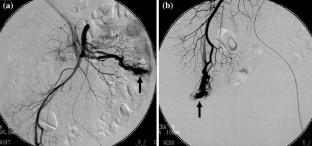

This report presents the case of a patient with Cowden syndrome who had arteriovenous malformations (AVMs) at the jejunum and the ileum and experienced intestinal bleeding. A 54-year-old Japanese male presented with general fatigue and melena. Endoscopic examinations showed gastrointestinal polyposis from the esophagus to the rectum. However, the site of bleeding was not identified. There were some papules on his face and neck. He also had macrocephaly and had multiple papillomas along the gum-line. These findings indicated a clinical diagnosis of Cowden syndrome. Enhanced computed tomography (CT) and angiography analyses indicated the presence of AVMs at the jejunum and the ileum. He was treated with partial resection of the jejunum and ileum including these two AVMs. This was a rare case of two AVMs involving the small bowel in a patient with Cowden syndrome. Enhanced CT was very useful and convenient for the detection of gastrointestinal AVMs in this case.

Fig. 2